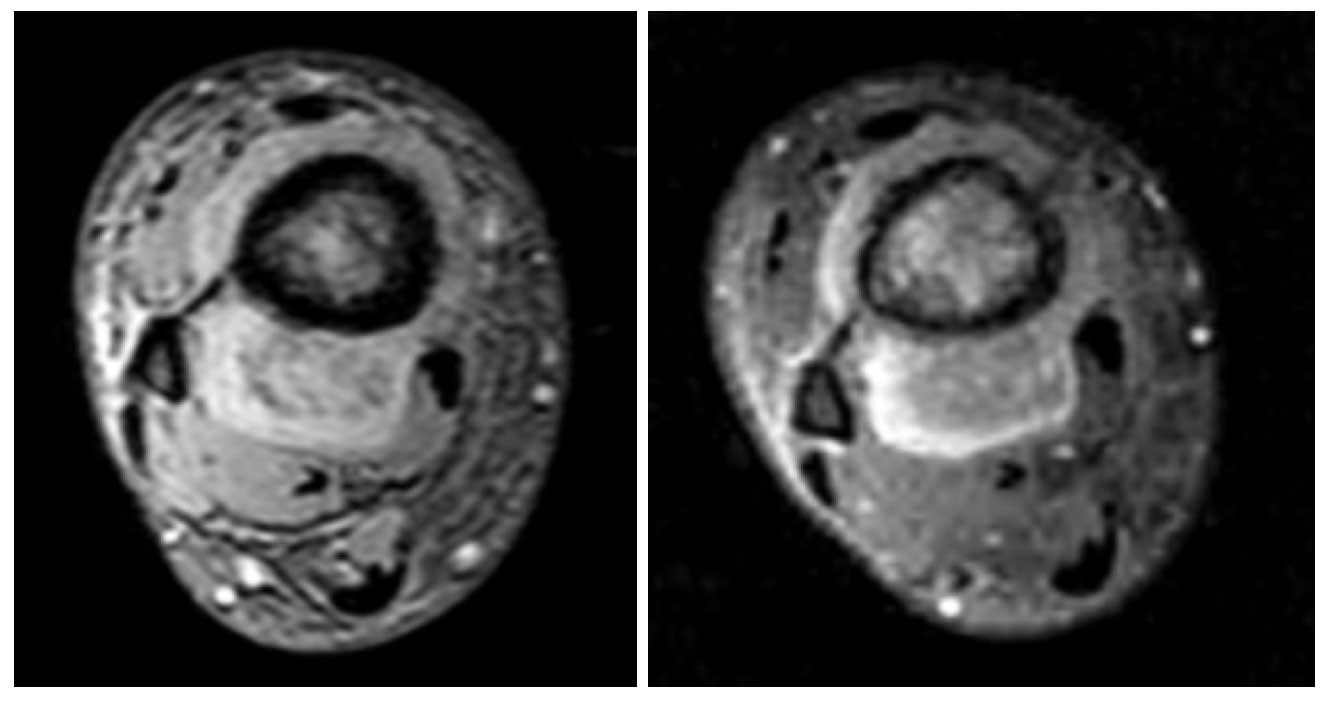

Ameliyat Öncesi: MR’da distal tibia çevresinde çepeçevre saran heterojen yumuşak doku komponenti görülmekte.